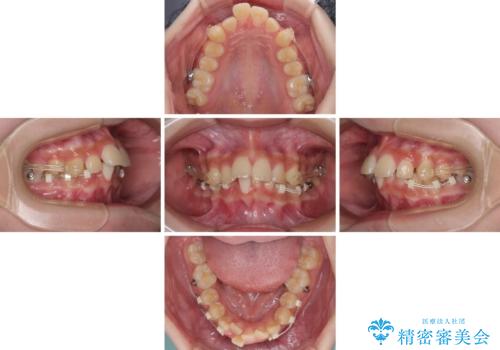

インビザライン単体で対応ることも検討できますが、達成する可能性が低いため、カリエールディスタライザーという補助装置を併用して、より確実性を上げることとしました。

奥歯の咬み合わせと深い咬み合わせを改善した後、インビザラインで歯列を整えることとしました。

ワイヤー装置と補助装置を有効に活用し、さらには高校生ということもあり、1年9か月で狙い通りの仕上がりを達成することができました。